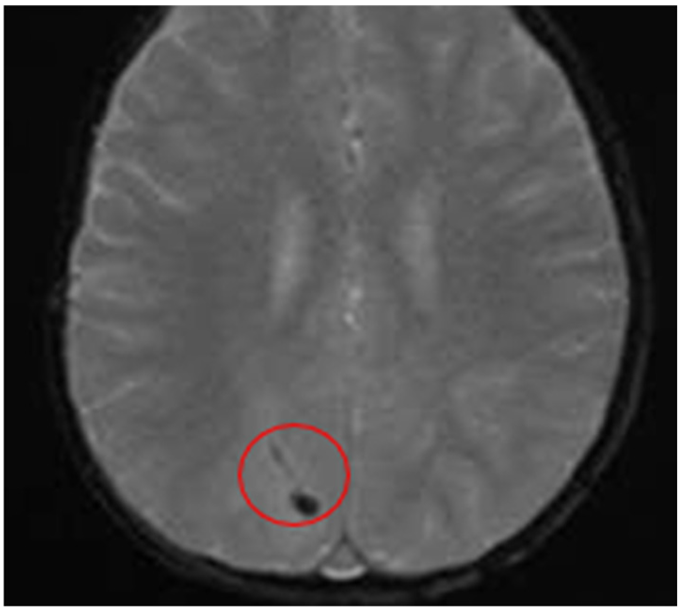

Quadrant B: T2 – FLAIR sequence

|

Hypointense Spots Are Evident in the Right Occipital Region ∙ Suggestive Findings of Hemorrhagic Collection |